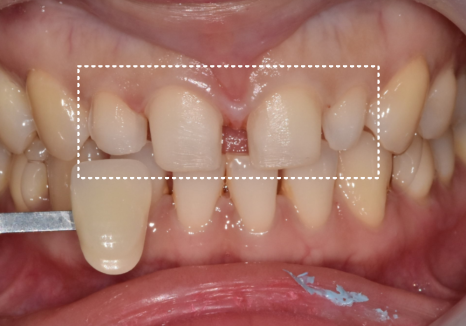

사례 2) 한 치아만 유달리 작아, 공간이 비어 보인 경우

강일동 라미네이트 가격 망설여질 때 꼭 확인해야 할 '이것'

두 번째 환자분은

앞니 크기나 배열 자체는 비교적 안정적이었지만,

한 치아만 크기가 작아

시선이 그쪽으로 모이던 경우였습니다.

241102

이 역시

한 개의 왜소치에 해당하는 상태였지만,

첫 번째 사례와는 구조가 달랐습니다.

앞니와 송곳니 사이가 멀어,

이미 어느 정도 공간이 확보돼 있었고,

왜소치로 인해 공간이 비어 있는 상태

앞니 전체의 크기와 배열도

전반적으로 균형이 잘 잡혀 있었습니다.

즉,

전체가 어색한 상태라기보다

한 지점만 살짝 비어 보이는 구조였습니다.